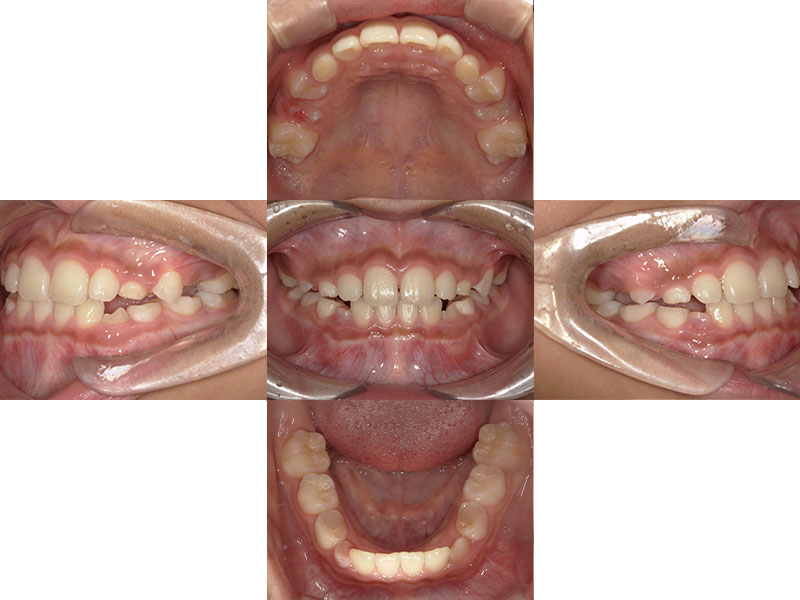

小児矯正

治療前

Before

治療後

After

年齢 10

性別 男児

主訴 下あごが出ている